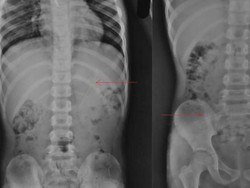

Tak terbayangkan oleh Muhamad Alalan (19), ia harus menjalani rawat inap di Rumah Sakit Umum Daerah (RSUD) Kabupaten Bima akibat didiagnosa perlengketan usus.